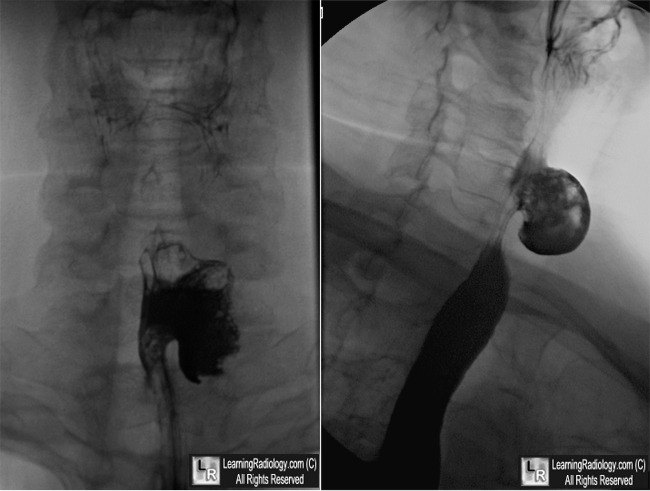

Killian-Jamieson Diverticulum

Imaging Findings

- Smooth-walled, contrast-containing pouch on barium swallow

- Most often unilateral and left-sided

- May be bilateral

Killian-Jamieson Diverticulum. Left: Frontal view from a barium swallow shows an outpouching of barium (white arrow) arising laterally from the cervical esophagus. Right: The diverticulum (yellow arrow) is anterior to the normal esophagus.